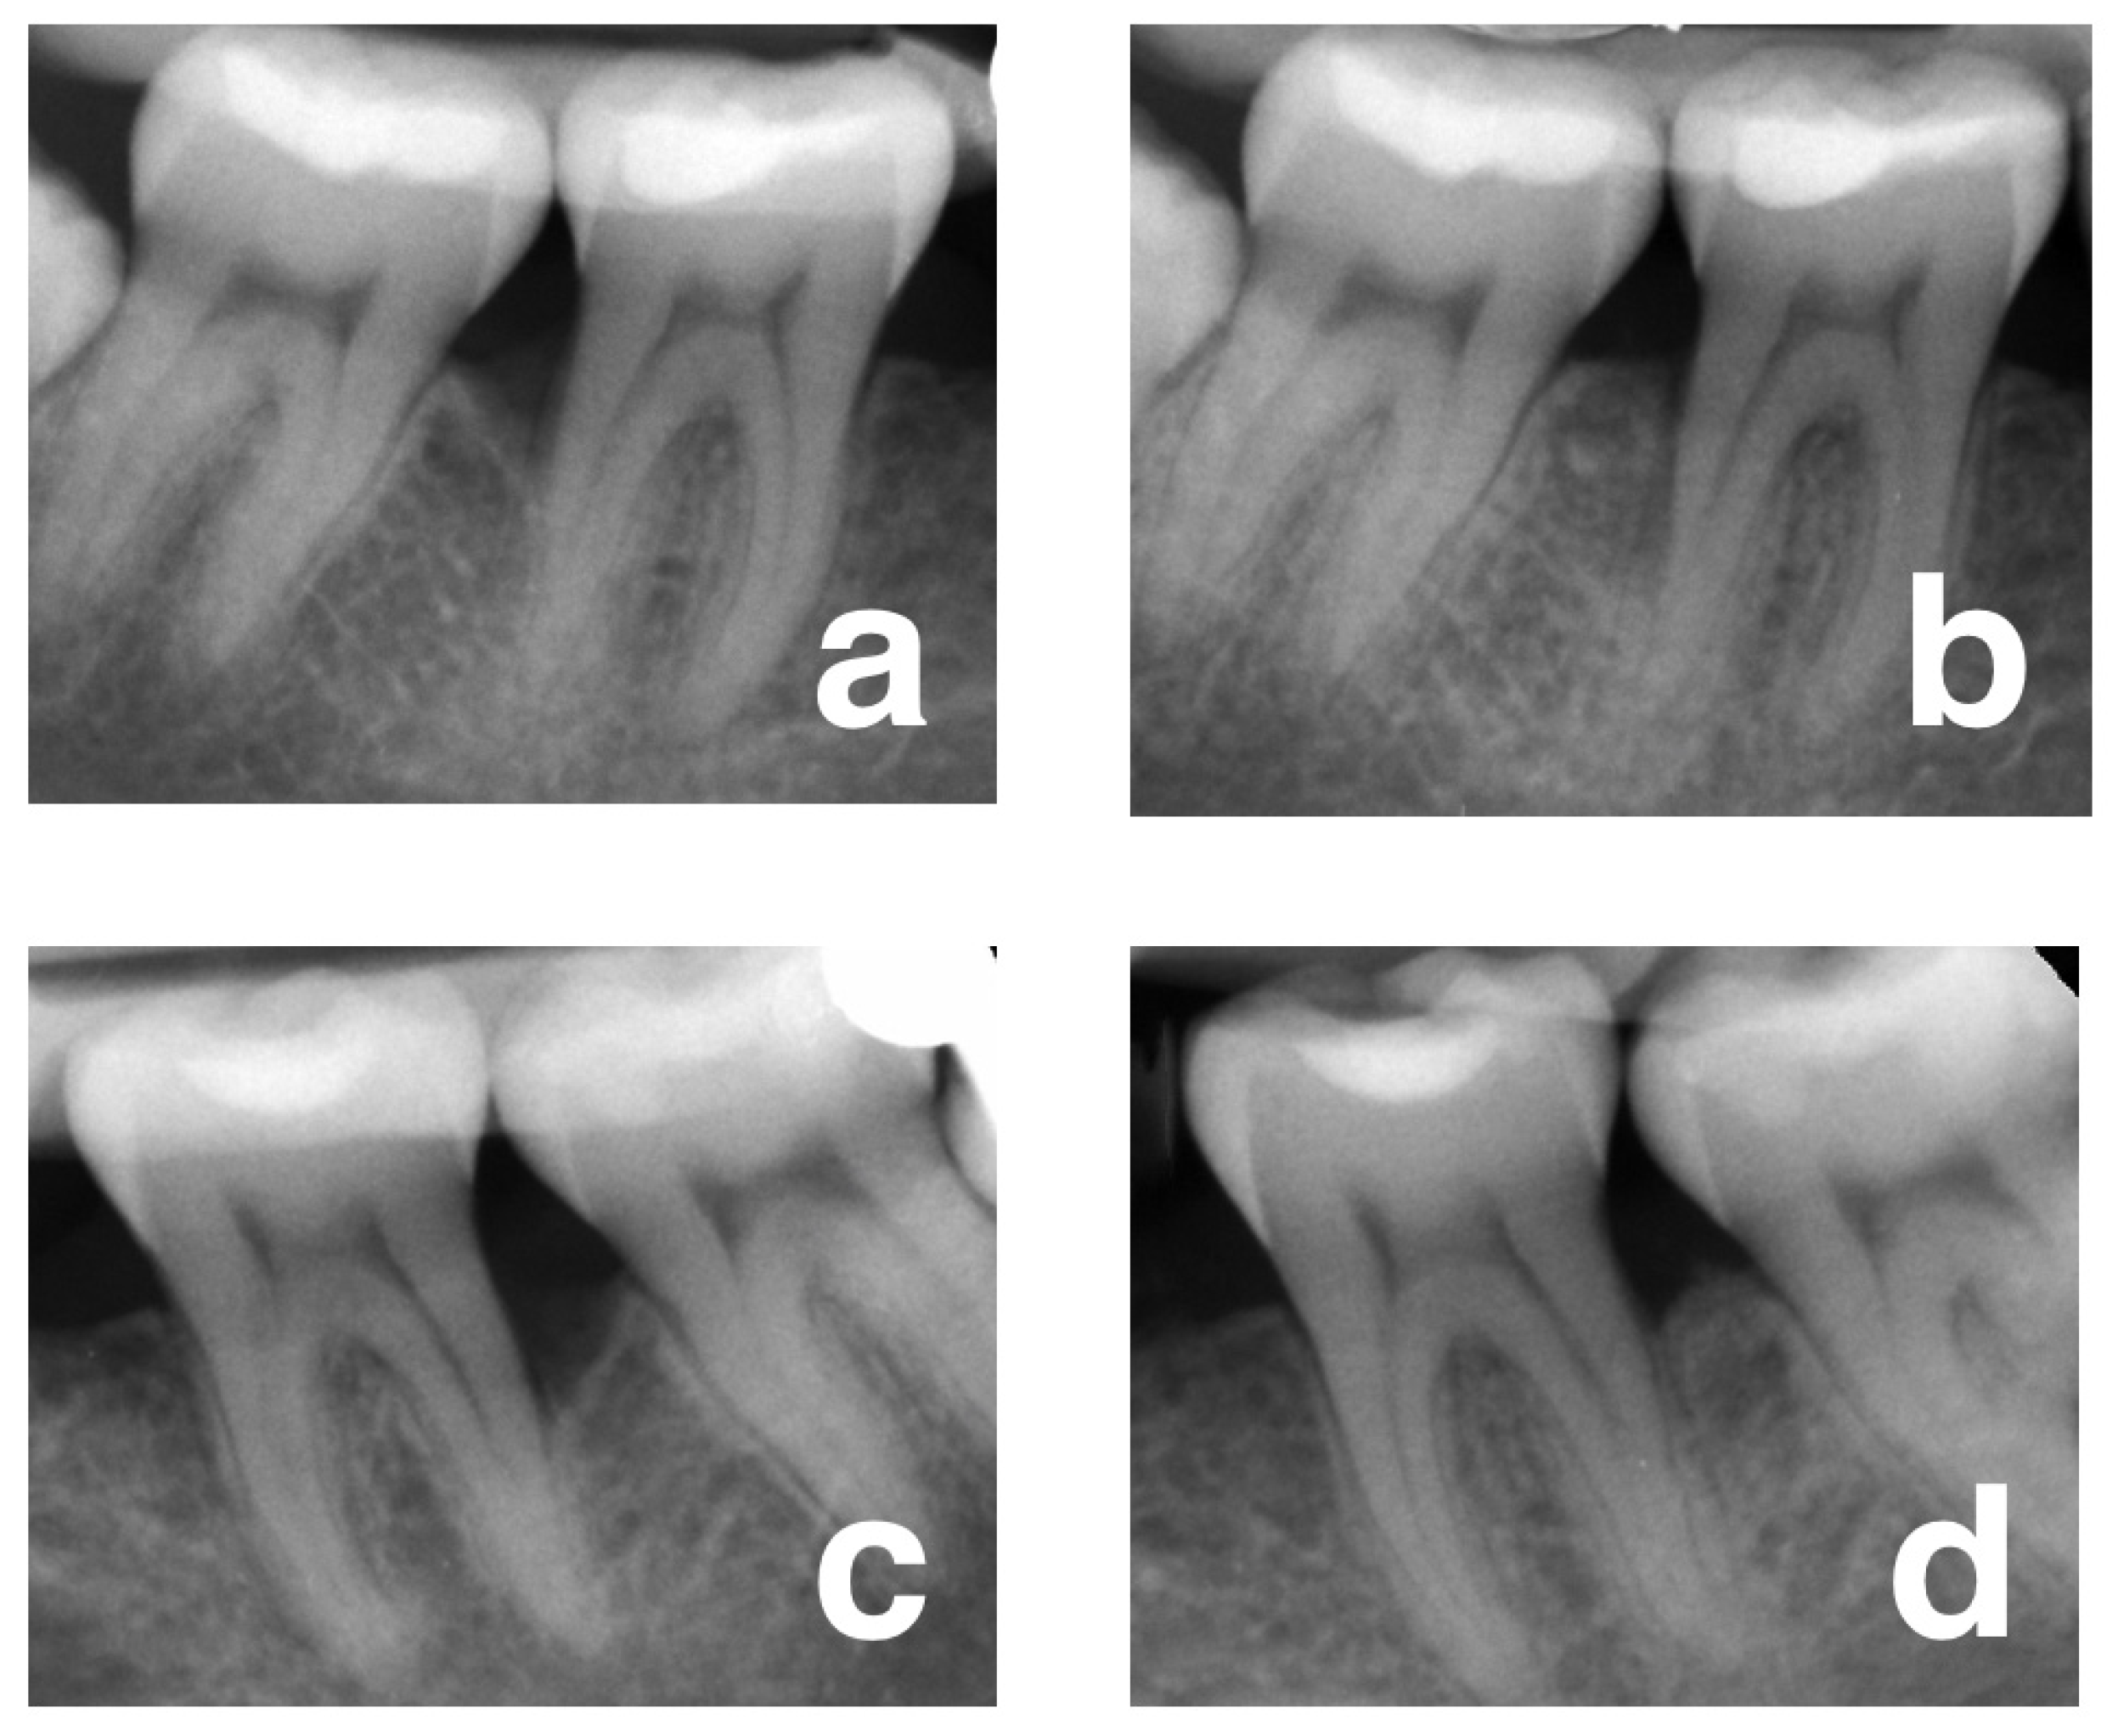

2.5. Radiological Outcomes

3.2. Changes in Clinical and Radiological Parameters